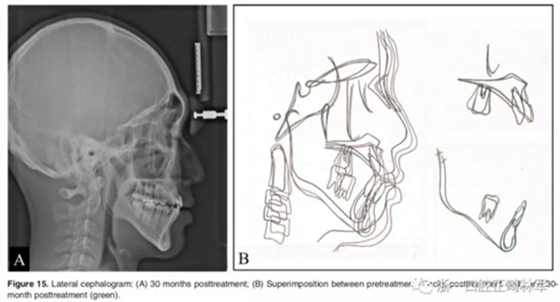

2年隨訪:咬合關(guān)系保持穩(wěn)定,無明顯復(fù)發(fā),下頜有一定晚期生長趨勢;前牙牙齦外形、牙冠高度無明顯變化;唇側(cè)牙槽骨高度、厚度均保持良好。